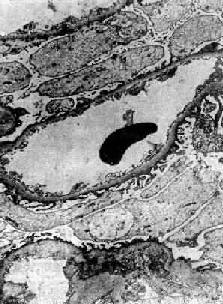

在电子显微镜下可见肾小球系膜细胞和内皮细胞增生肿胀。基底膜和脏层上皮细胞间有致密物质沉积。这些沉积物大小不等,有的很大,在基底膜表面呈驼峰状或小丘状(图12-8,图12-9)。沉积物表面的上皮细胞足突多消失。基底膜变化不明显有时边缘稍不规则。沉积物一般在发病后几天就可出现,在4~6周内消失。有时基底膜内侧内皮细胞下和系膜内也可见小型沉积物。

图12-8 毛细血管内增生性肾小球肾炎

电镜下见肾小球毛细血管基底膜表面上皮细胞下有多数驼峰状电子致密沉积物

图12-9 毛细血管内增生性肾小球肾炎

电镜下见驼峰状沉积物位于毛细血管基底膜表面。沉积物表面有上皮细胞覆盖,上皮细胞足突消失